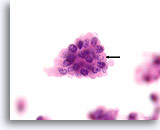

Afbeelding 19

Cellaesie, folliculair neoplasma (lymfocytische thyroïditis vs hurthlecelneoplasma) kan niet worden uitgesloten, schildklier FNA, ThinPrep®.

De hurthlecellen hebben een microfolliculaire organisatie. Er zijn een paar lymfocyten door het epitheel gemengd, hetgeen pleit voor lymfocytische thyroïditis.

60X

Afbeelding 19

Cellaesie, folliculair neoplasma (lymfocytische thyroïditis vs hurthlecelneoplasma) kan niet worden uitgesloten, schildklier FNA, ThinPrep®.

De hurthlecellen hebben een microfolliculaire organisatie. Er zijn een paar lymfocyten door het epitheel gemengd, hetgeen pleit voor lymfocytische thyroïditis.

60X